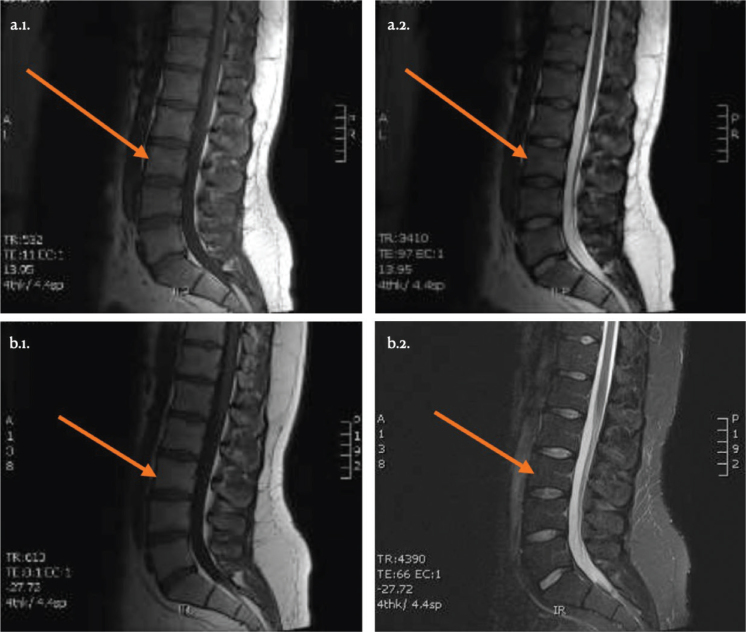

Methods: Six participants with chronic low back pain and lumbar degenerative intervertebral disc (monodiscopathy) disease underwent 1 Platelet-Rich Plasma injection, with a 1-year follow-up. Platelet-Rich Plasma injections were administered into the lumbar intervertebral disc, and outcomes were measured using the Roland Morris Disability Questionnaire, numeric rating scale for pain, Tampa scale for kinesiophobia and lumbar flexion range. Magnetic resonance imaging analysis assessed disc changes.

Results: No adverse events were reported. At the end of the 1-year follow-up, half of the patients showed significant improvements in disability scores at 1 year, while 3 of the 6 patients had no change. Magnetic resonance imaging revealed no significant disc changes.